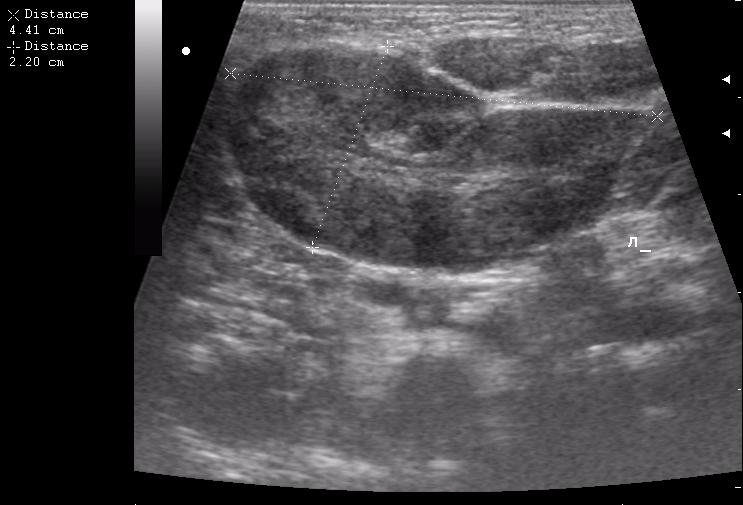

пакеты гиперплазированных лимфоузлов

лимфоузел в правой подчелюстной области